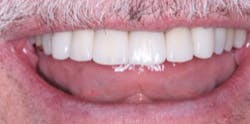

Figure 2: A comparison of PFM with all-ceramic restorations. Base your own decisions on both history and the research on all-ceramic restorations as summarized in the state-of-the-art information in this article.